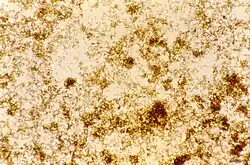

Plasmodium ovale microgametocyte in Giemsa-stained thin blood film, with annotated Schüffner's dots and hemozoin pigment.